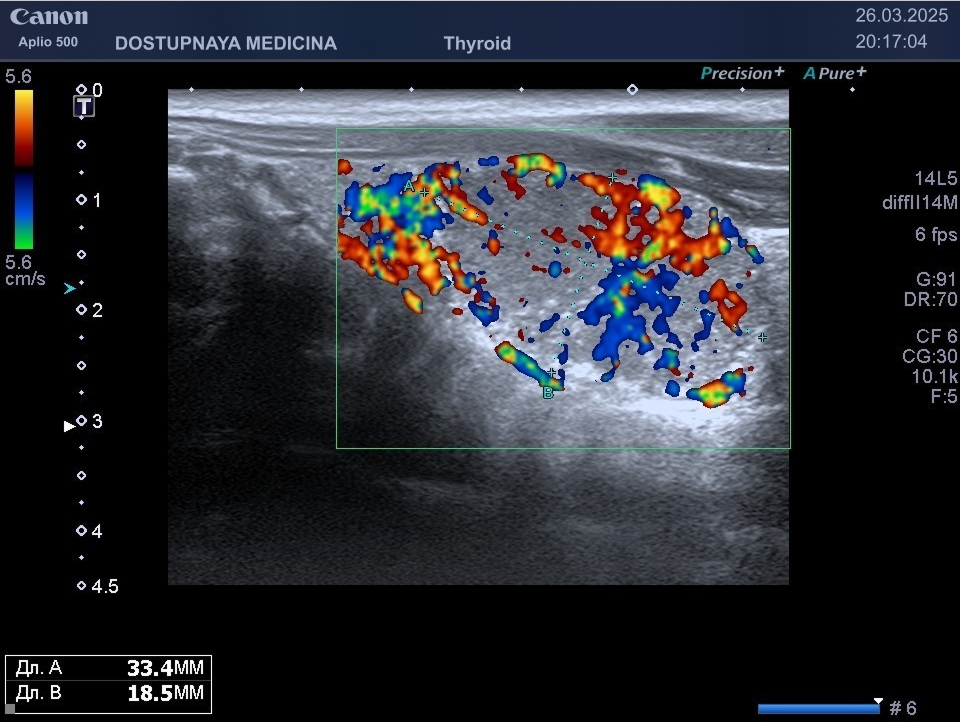

В ультразвуковой диагностике существует классификация образований щитовидной желзы по TIRADS, которая по различным критериям определяет степень онкоопастности того или ионого узла. При оценке учитывается эхоструткура образования ( кистозная, губчатая, солидная или солидно-кистозная), эхогенность ( анэхогенное, гиперэхогенное, гипоэхогенное), пространственная ориентация горизонтальная, вертикальная, неопределённая), контуры образования (ровные, дольчатые, зазубренные с острыми углами), наличие эхогенных включений( макрокальцинаты, микрокальцинаты, периферическая кольцевидная кальцификация). В зависимости от этих критериев выделяют различные категориии объёмных образований в щитовидной железе:

Большинство узловых образований в щитовидной железе не нуждаются в лечении и требуют лишь наблюдения путём повторного ультразвуковых исследований.

При подозрении на озлокачествление и увеличении узла в размерах требуется тонкоигольная пункционная биопсия с полседующим цитологическим исследованием, полученного материала.

Лечение рака щитовидной железы хирургическое. Показана в зависимости от конкретной клинической ситуации либо тиреоидэктомия (удаление всей щитовидной железы), либо гемитиреоидэктомия (удаление одной доли щитовидной железы)